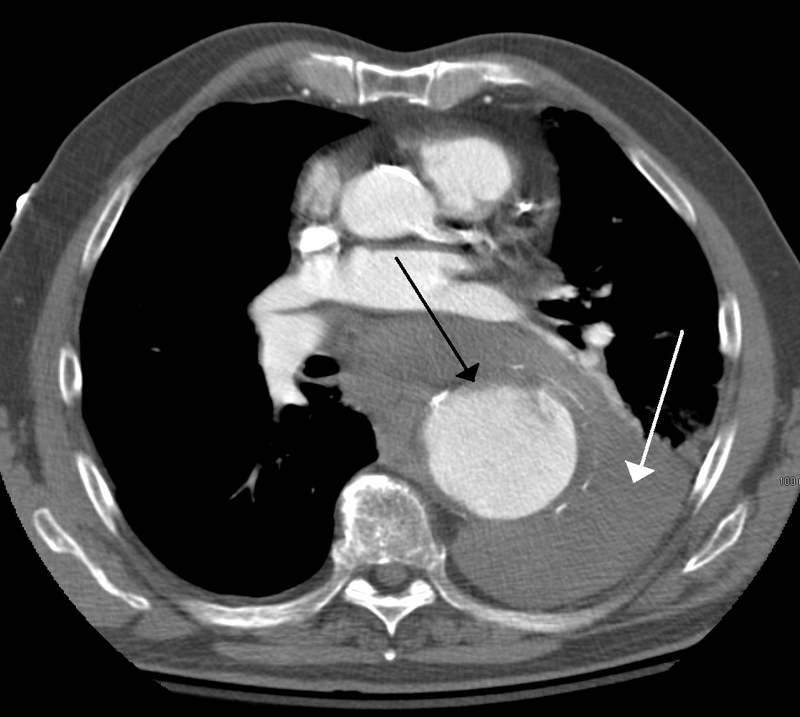

Aortic Dissection

Aortic dissection is caused by shearing force allowing blood leaking through the media of the aortic wall due to an intimal tear.

Aortic dissection occurs in the high-stress zone of the proximal portion of the aorta and is accompanied by medial weakening.

Risk factors of aortic dissection include:

- Hypertension in elderly persons, characterized by vasa vasorum hyaline arteriosclerosis

- Genetic connective tissue abnormalities in younger individuals such as Marfan syndrome or Ehlers-Danlos syndrome, characterized by weak connective tissue and cystic medial degeneration

The media sags as a result of decreased flow.

Weakness of the connective tissue in the media is a characteristic symptom of Marfan syndrome and Ehlers-Danlos syndrome (cystic medial necrosis).

Symptoms of aortic dissection include:

- Intense chest pain

- Chest pain that radiates to the back

Complications of aortic dissection include:

- Death secondary to cardiac tamponade (the most common)

- Rupture with lethal hemorrhage

- Obstruction of branching arteries (such as the coronary or renal arteries)

- End-organ ischemia